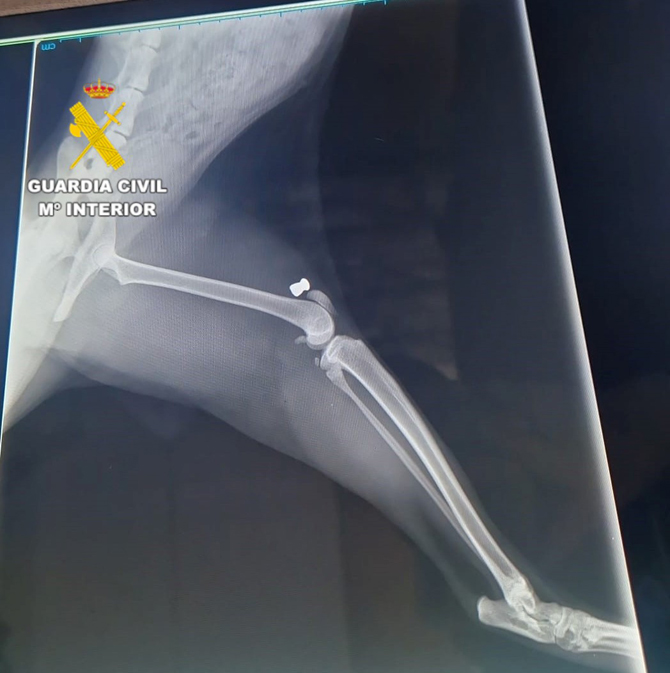

La investigación se inició durante el mes de septiembre, cuando la Patrulla del SEPRONA tuvo conocimiento del fallecimiento de varios felinos en el municipio. Tras realizar las primeras pesquisas, los agentes comprobaron que las lesiones eran compatibles con impactos de perdigones procedentes de una carabina de aire comprimido.

Un examen veterinario confirmó la hipótesis, al hallar varios perdigones incrustados en el cuerpo de los animales.